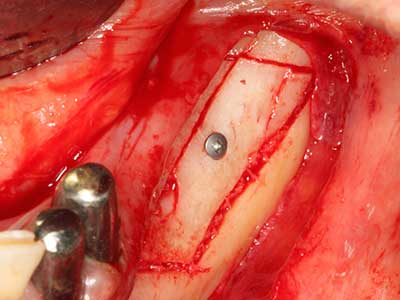

En la extracción de bloques óseos la piezocirugía también presenta ventajas adicionales: Además de la alta precisión en la osteotomía que ya se ha descrito antes, se ha comprobado que el uso de los delgados insertos de sierra resulta especialmente cuidadosas con el hueso. Frente a esto, sobre todo cuando se usan las fresas de Lindemann, cabe esperar pérdidas en la extracción significativamente más altas debido al mayor grosor de la parte frontal del cabezal (Lakshmiganthan, Gokulanathan et al. 2012). La separación basal que se necesita en particular en los injertos de bloque extraídos de forma retromolar se ve facilitada mediante sierras perpendiculares especialmente previstas a tal fin, lo que permite considerar que la cirugía piezoeléctrica es un procedimiento preciso y seguro para la obtención de bloques de hueso en el área retromolar (Happe 2007) (fig. 1-12).

Como ya se ha demostrado en el pasado, básicamente cualquier procedimiento de cirugía de hueso representa una posible indicación para la cirugía piezoeléctrica. Así, la preparación del segmento móvil en la osteogénesis de distracción (fig. 23-25) y en la osteotomía de sándwich puede realizarse con piezas especiales, sin poner en peligro el suministro sanguíneo de la parte crestal, que resulta esencial para el éxito de ambas técnicas (González-García, Diniz-Freitas et al. 2008).

En la cirugía del seno maxilar surgen otros campos de aplicación: En este punto, tras la preparación concéntrica de una tapa ósea de la pared del seno maxilar (que suele tener forma trapezoidal), es posible eliminar patologías y cuerpos extraños del seno maxilar. La tapa ósea se repone después de finalizar la parte intra-antral de la operación y se asegura frente a una posible dislocación mediante cuñas o suturas adaptables.